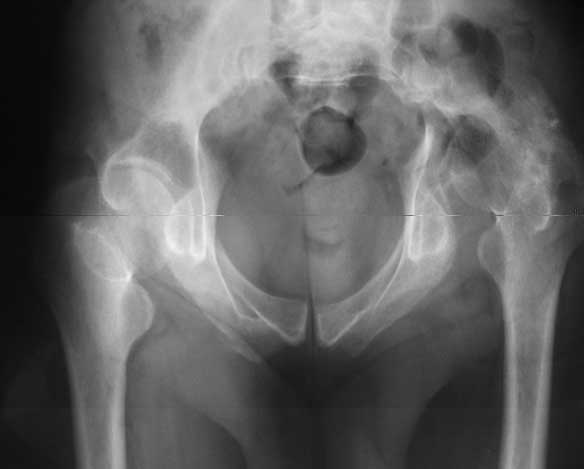

Our experience showes, that reposition and stabilization pelvis in zone of old acetabular fractures with bone grafting are very traumatic and not effective due head AVN and hip arthrosis.

In such cases we use hip arthroplasty with "Octopus" acetabular system (De Puy). This system consist of acetabular ring and cementless cup.

It`s allow you to fix the reinforcement ring in proper position, then bone grafting of the defects of the acetabulum walls and floor.

Then you fix the cup to the ring.

I will show some cases.